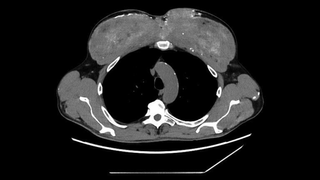

A man's muscles looked strangely deformed. Doctors found they were leaking calcium into his blood.

A man showed up to the hospital with vomiting, weakness, failing kidneys and sky-high calcium. The culprit was a muscle-enhancing oil he injected into his chest and arms years ago.